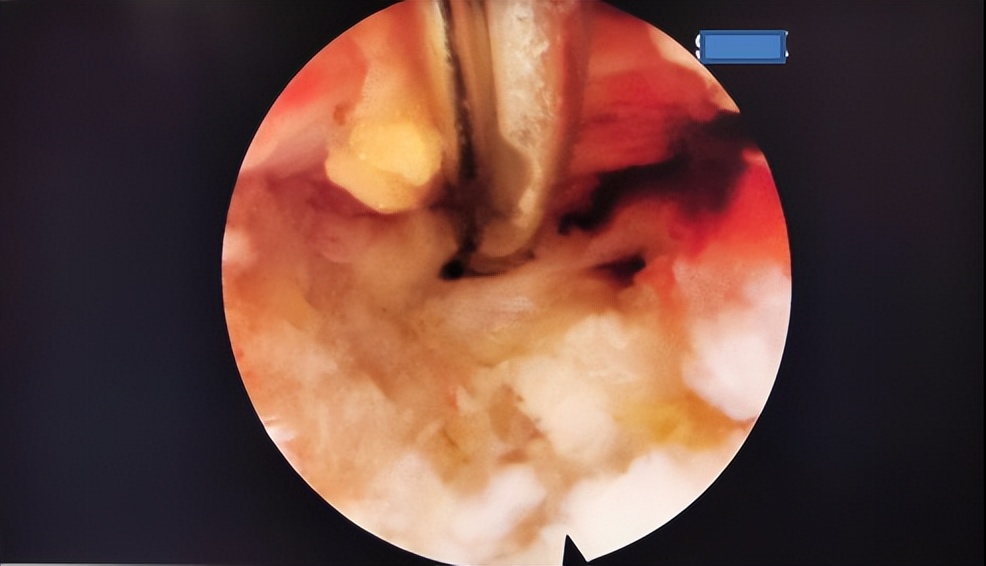

4月14日,在麻醉科皮鑫医生的基础监护下,王大为副教授顺利进行了局部麻醉和定位。在王大为副教授、鄂晓强副教授、刘伟副教授的通力配合下,历时两个多小时,成功完成腰椎后路椎板间入路经皮微创孔镜下髓核摘除椎管减压术,成功摘除大量突出间盘组织,解除神经根压迫。术后腰腿疼痛症状完全消失,患者在手术室即刻便可自由下地行走,两日后就康复出院。

术中镜下操作视野良好,摘除多量髓核和间盘组织